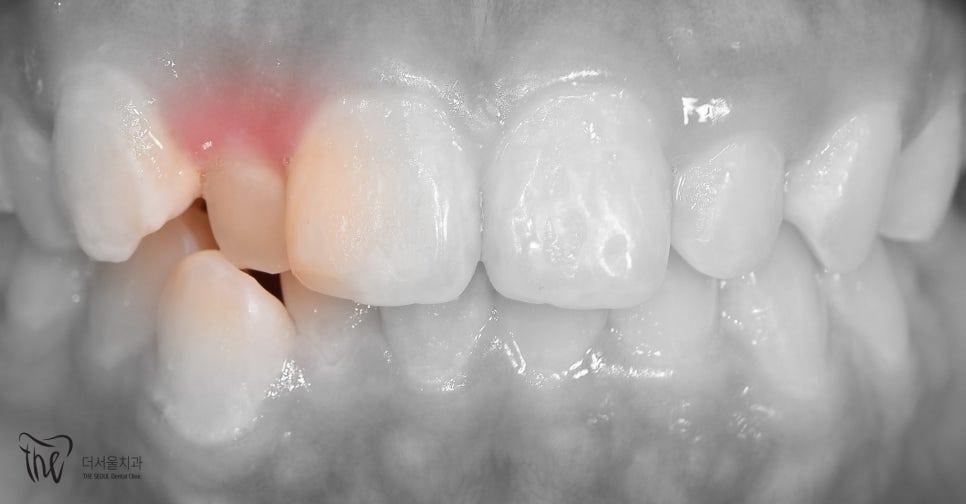

부정교합 이라는 것은 꼭 아랫니가 윗니보다 앞쪽에 위치 된 것을 뜻하는 것은 아닙니다. 윗니와 아랫니가 맞물리면서, 교합관계를 형성하는데 그

부정교합 2급 이라는 것은, 하악보다 상악이 더 전방에 위치되거나 또는 상악의 치아들이, 하악 치아들보다 더 앞쪽에 위치되어 있는것을 뜻하며

증세를 갖고 계셨던 분의 임상 증례를 보여드립니다. 교정 치료를 통해서 2급 부정교합이 개선 되었으며 치료를 끝으로, 턱 끝에 보형물